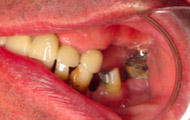

Situation clinique initiale

Situation clinique terminée